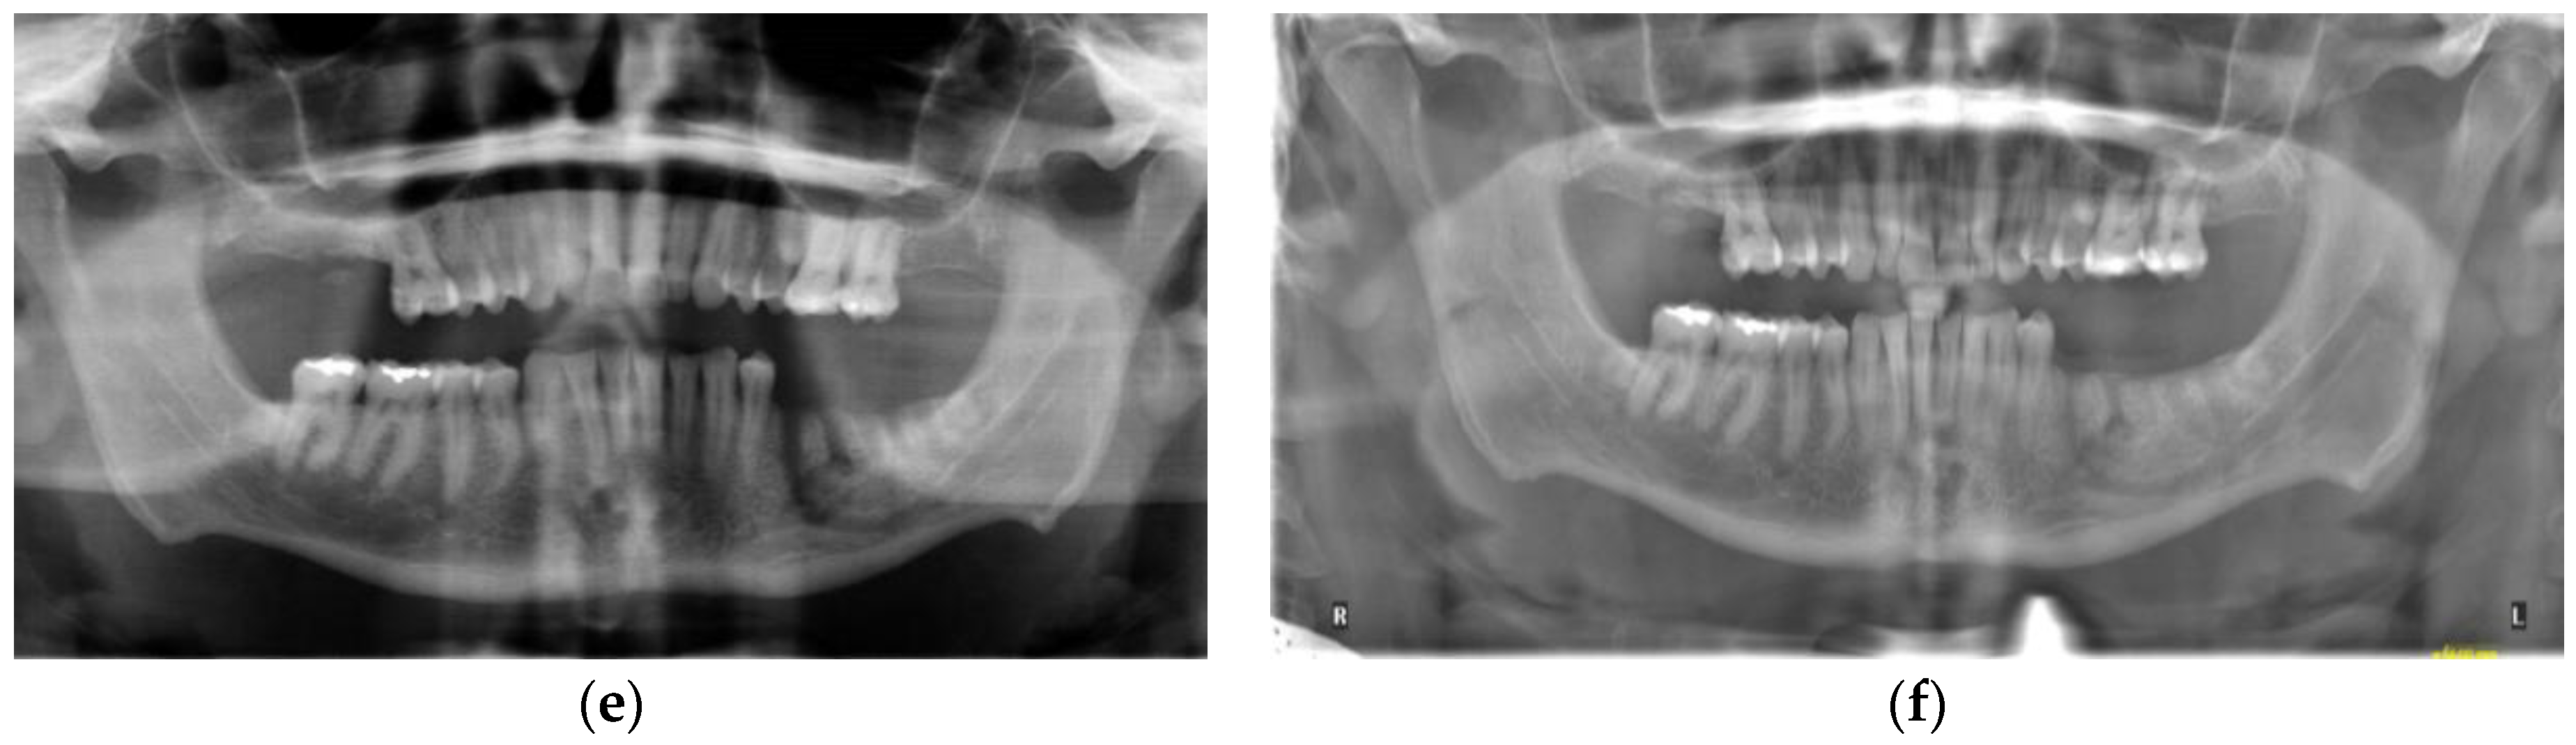

3.1. Case 1

3.2. Case 2